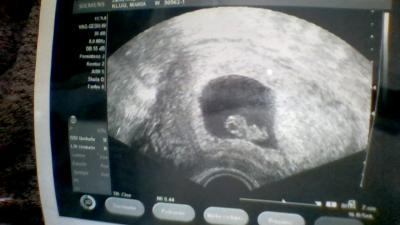

gestern beim Us hat er sich von beiden seiten zeigen lassen :-)

Bild zu unser muckelchen - Forum für August - Mamis